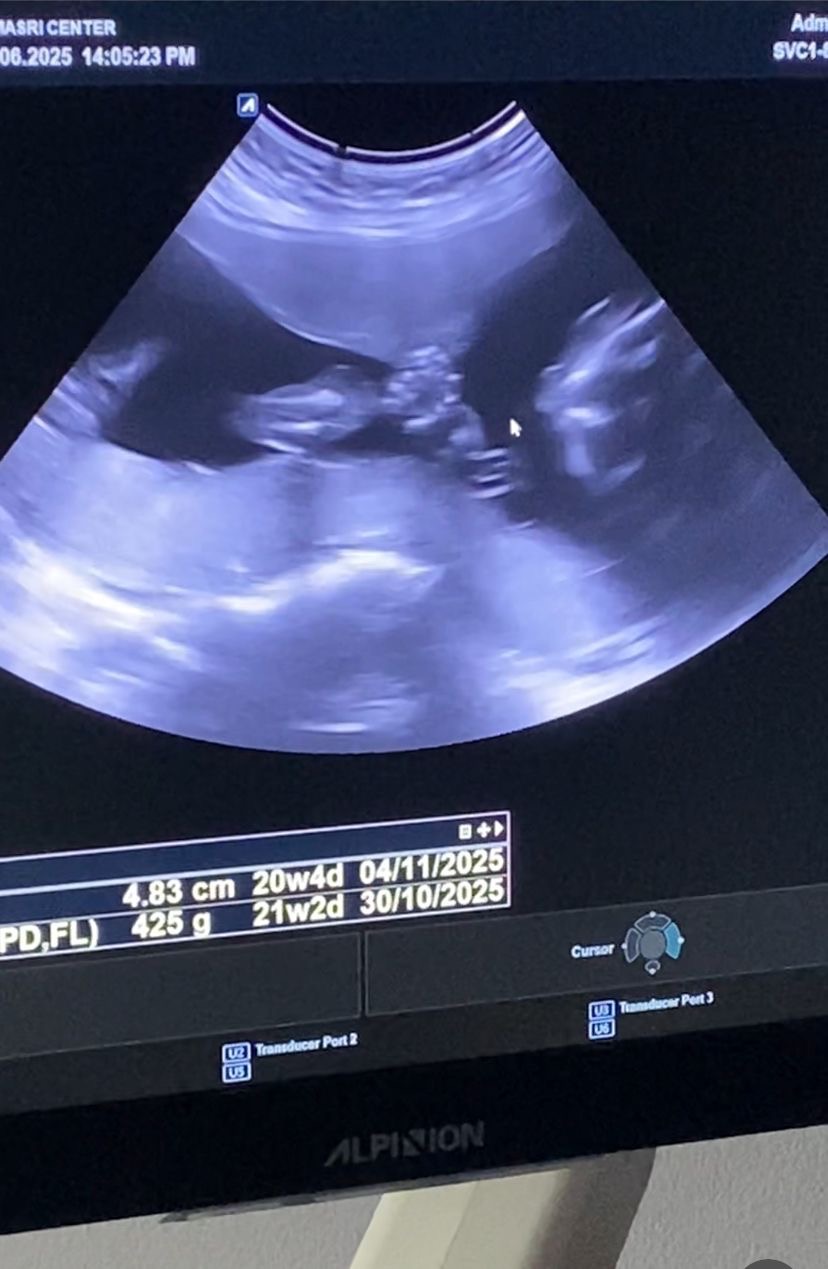

My name is Reem Ramadan, I am a dentist from Gaza, a mother to my little daughter Salma, and currently pregnant with my second child.

My husband has no work, and I have lost my clinic. With no income, survival is almost impossible. What breaks my heart the most is seeing my daughter grow up knowing nothing but fear, hunger, and displacement — and fearing for the baby I carry, wondering what kind of life will await them in such harsh and terrifying conditions. Every night, we live in fear of bombings, and every day is a fight against hunger and hopelessness.

• Access medical care during my pregnancy and after childbirth.